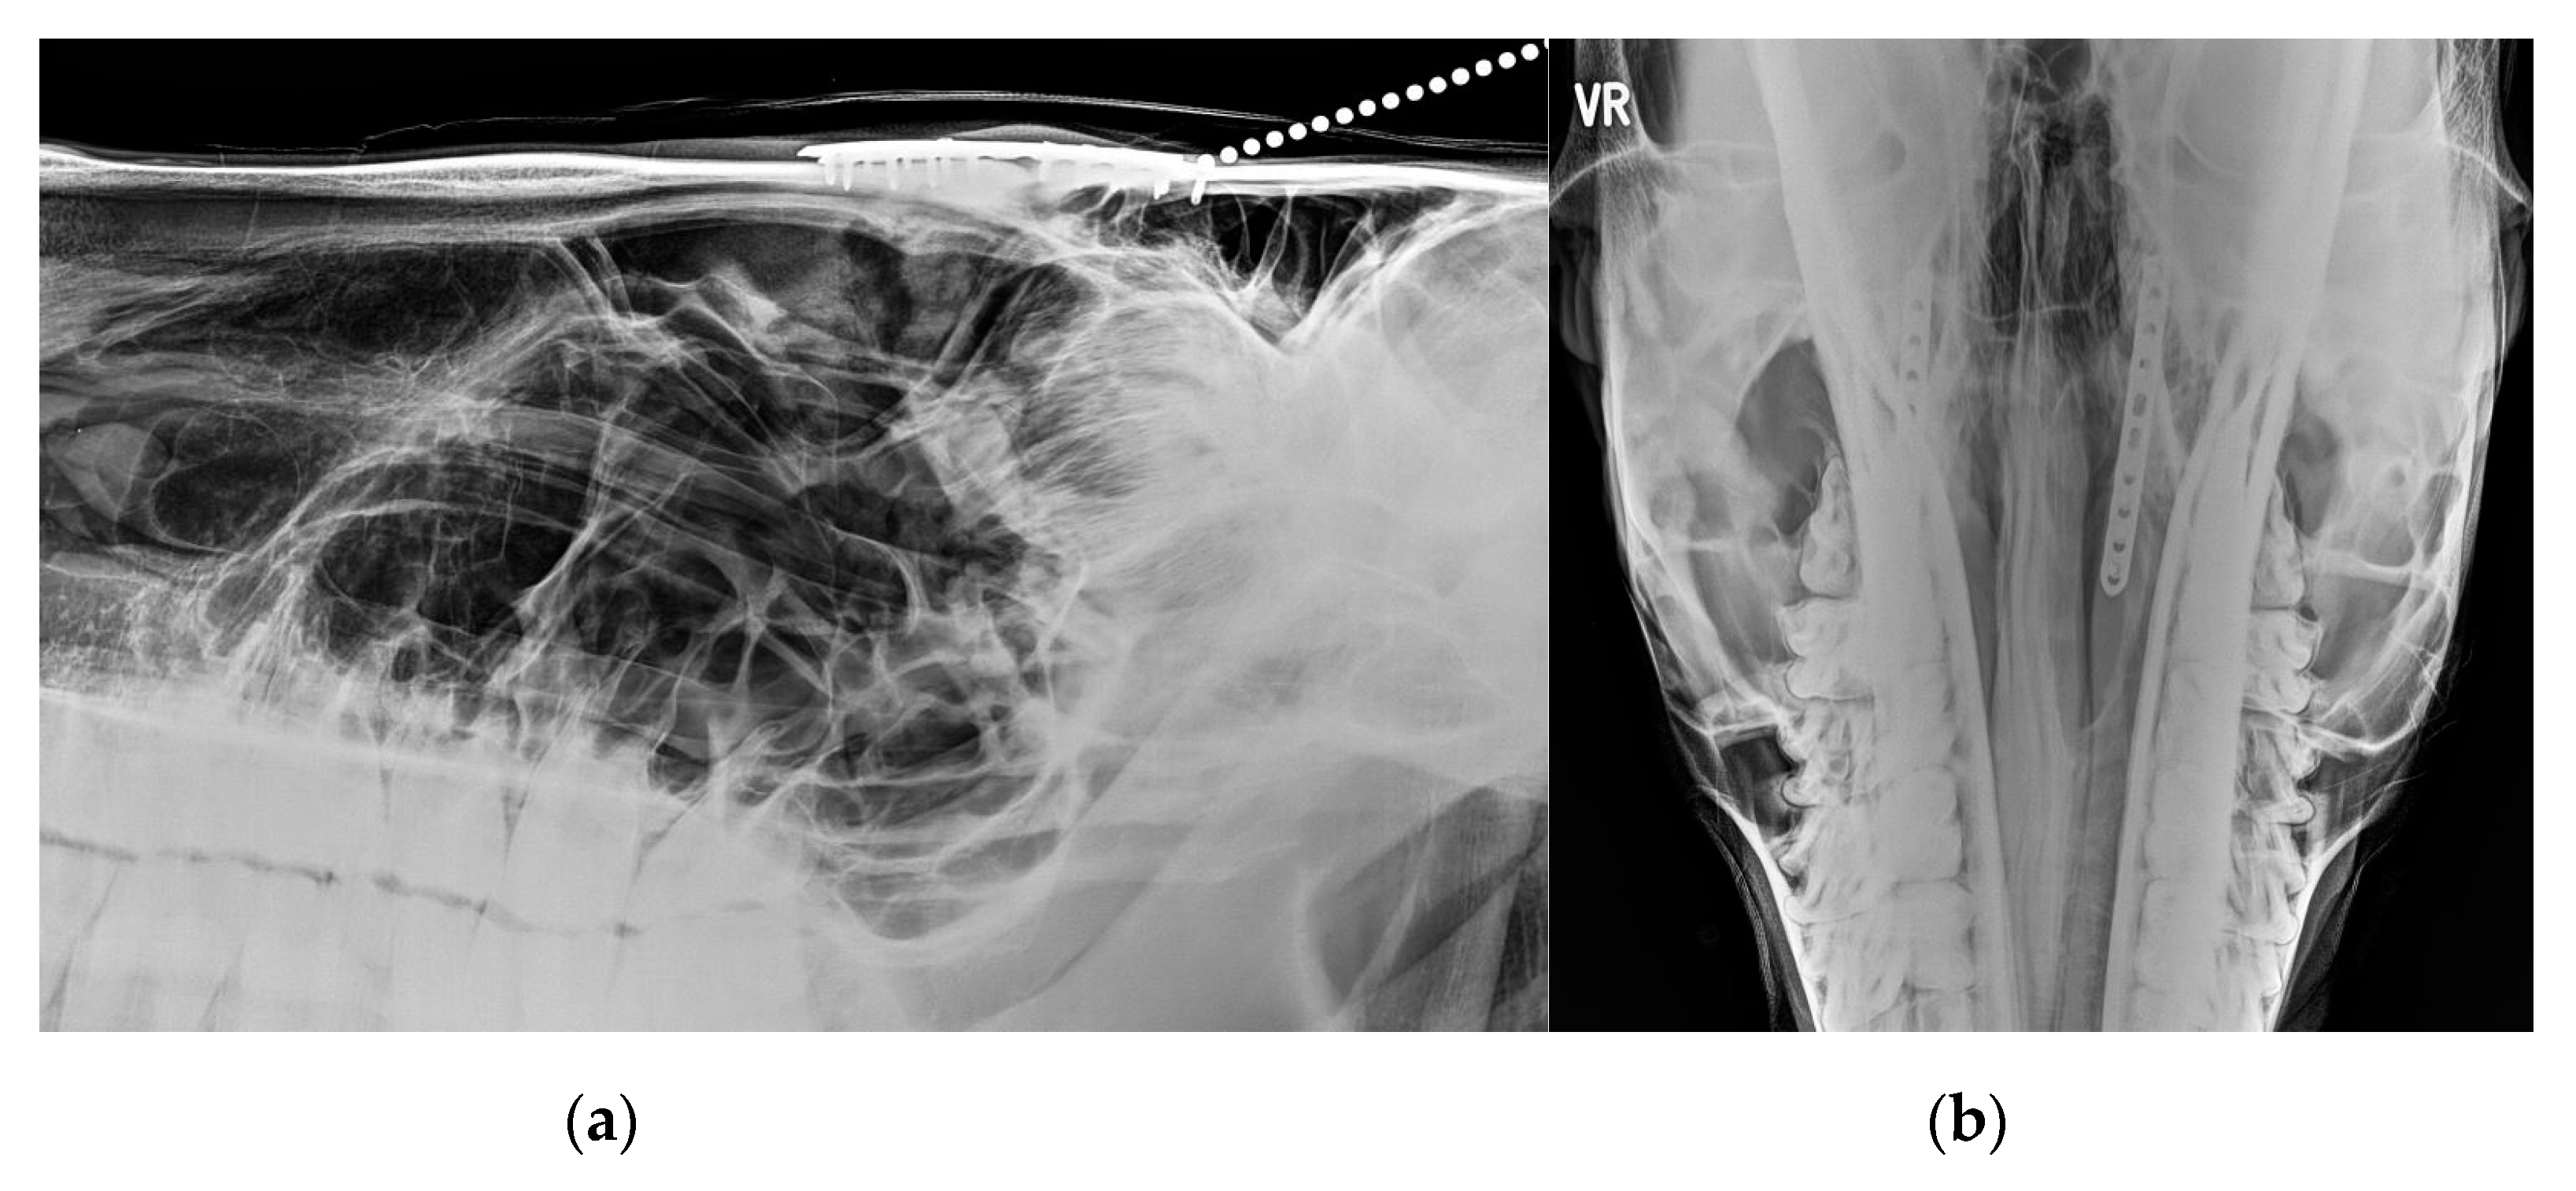

3.2. Imaging Findings

3.3. Treatments